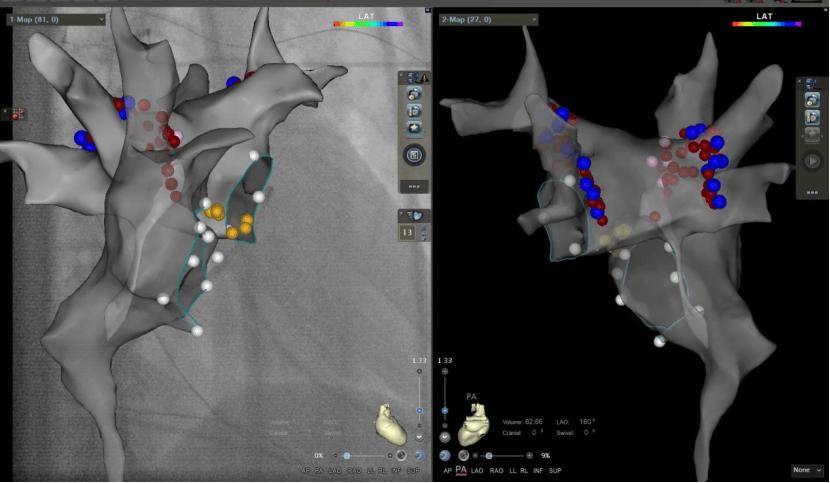

术中心脏三维模型及迷走神经节区域消融

为了给孩子一个更好的未来,心血管内科主任石琳决定为强强施行迷走神经节消融术,这是一种新的微创治疗方法,目前仅在少数几家知名的儿童心血管中心才能开展。整个手术不到1个小时,强强的“心病”得到治愈。术后监护仪规律跳动着80次/分的窦性心律,复查心电图一切正常,强强第二天就戴着动态心电监测仪下床活动,原本频繁出现的房室传导阻滞现象完全消失。

心血管内科经过多年的研究、实践,掌握了采用心脏迷走神经节消融术来治疗自主神经介导的房室传导阻滞和晕厥的方法。心脏迷走神经节消融术是一项非常前沿的微创介入手术,较传统起搏器植入手术具有安全、有效、痛苦小等优势,可节省近一半的治疗费用,不仅避免了永久起搏器植入带来的运动限制、电池更换等沉重经济负担,更重要的是通过重构自主神经平衡,一劳永逸地解决晕厥等危险。